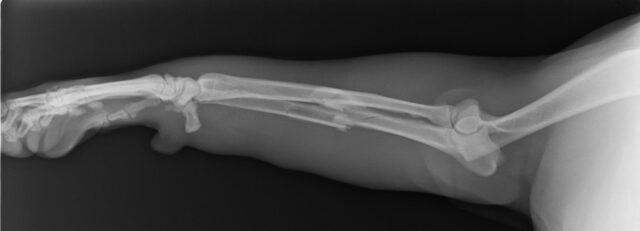

基本的にはレントゲン検査によって確定診断を行います。

橈尺骨骨折